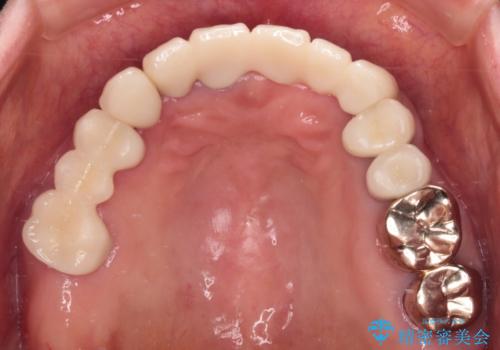

- 抜歯の必要な前歯や、以前治療した前歯のクラウンの外観を気にして来院された患者様です。

上顎犬歯や下顎大臼歯は、必要なところはインプラントを埋入することとしました。

クラウンが不適合であったり、根管治療の必要なほどの痛みのある歯であったり、見た目の気になる前歯などをオールセラミッククラウンに補綴治療を行うこととしました。